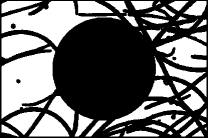

From the fuzzy sets , and three grey probability images are generated , and of in size and a greyscale in . These are defined as follows: , , and

. Evidently, ,

.

These probability images show the pixel probabilities in graphic format, also taking advantage of the fact that as there are three images, a color image can be built by assigning the to the red channel, to the green channel and to the blue channel. This new image is equivalent to the three probability images and enables the result of the fuzzy classification of pixels to be seen much more clearly in graphic format, all of which is shown in Fig. 3.